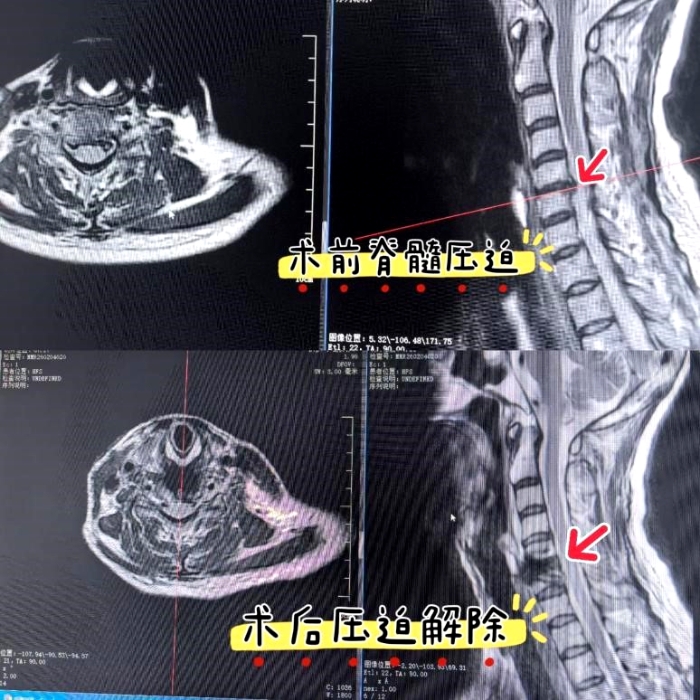

术前准备就绪,在麻醉科与手术室的密切配合下,手术顺利开展。术中,在高清内镜放大视野下,神经根、硬膜囊及周围血管等重要结构清晰可辨,显著降低了神经血管损伤风险;持续水介质的冲洗与清创也有效减少了术中出血。术后患者颈痛及上肢麻木症状迅速缓解,次日即可下地活动,康复周期较传统手术缩短一半以上。术后影像复查显示,椎间盘切除彻底,脊髓受压完全解除,内置物位置良好,手术达到预期效果。